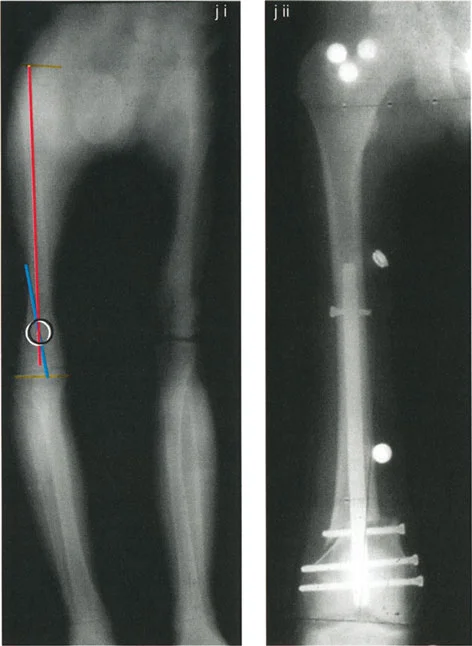

The Center of Rotation of Angulation (CORA) represents the apex of the deformity. To find the CORA, the surgeon draws the Proximal Mechanical Axis (PMA) line and the Distal Mechanical Axis (DMA) line.

* The PMA is drawn by taking the normal joint orientation angle from the proximal joint and extending a line down the shaft.

* The DMA is drawn by taking the normal joint orientation angle from the distal joint and extending a line up the shaft.

* The exact point where the PMA and DMA intersect is the CORA.

A bone may have a single CORA (unapical deformity) or multiple CORAs (multi-apical deformity). Identifying the precise location of the CORA is the prerequisite for determining where to cut the bone and how to hinge the correction.

- Perform the Malalignment Test Draw the mechanical axis from the center of the femoral head to the center of the ankle. Measure the MAD. Determine if the mechanical axis falls in the medial, lateral, or central zone of the knee.

- Perform the Malorientation Test Draw the individual mechanical axes of the femur and tibia. Measure the mLDFA, MPTA, LPFA, and mLDTA. Compare these to normal values to isolate the source bone of the deformity.

- Locate the CORA Draw the Proximal Mechanical Axis (PMA) and Distal Mechanical Axis (DMA) using the normal joint orientation angles. Mark their intersection as the CORA.

- Select the Osteotomy Rule Determine if the bone can be safely cut at the CORA (Rule 1) or if the cut must be moved to the metaphysis (Rule 2).

- Choose the Osteotomy Sequence Decide between an opening wedge, closing wedge, or dome based on limb length discrepancy and soft tissue constraints.

- Simulate the Correction Using digital templating software, digitally cut the bone, place the ACA, and rotate the segment. Verify that the final mechanical axis passes through the center of the knee and that joint lines are parallel to the floor.